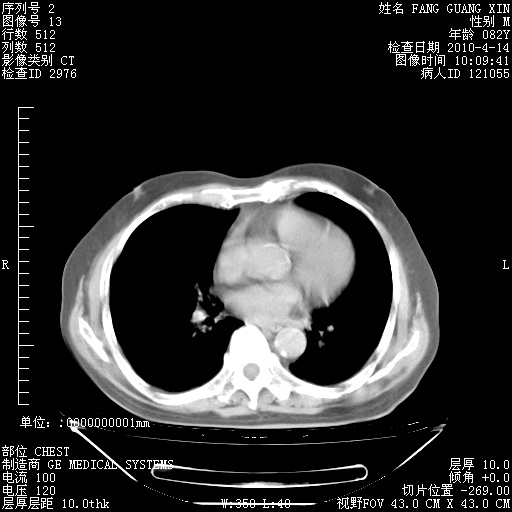

4月14日肺部CT

肺部CT平扫未见异常。